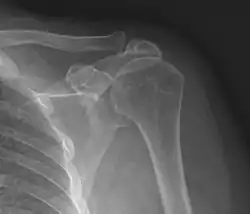

Plain x-rays of the shoulder can be used to detect some joint pathology and variations in the bones, including acromioclavicular arthritis, variations in the acromion, and calcification. However, x-rays do not allow visualization of soft tissue and thus hold a low diagnostic value.[2] Ultrasonography, arthrography and MRI can be used to detect rotator cuff muscle pathology. MRI is the best imaging test prior to arthroscopic surgery.[2] Due to lack of understanding of the pathoaetiology, and lack of diagnostic accuracy in the assessment process by many physicians,[21] several opinions are recommended before intervention.